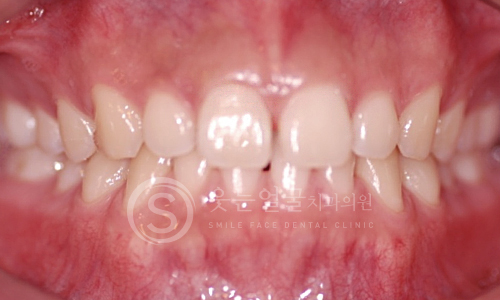

한눈에 보는

치아교정 전후사진